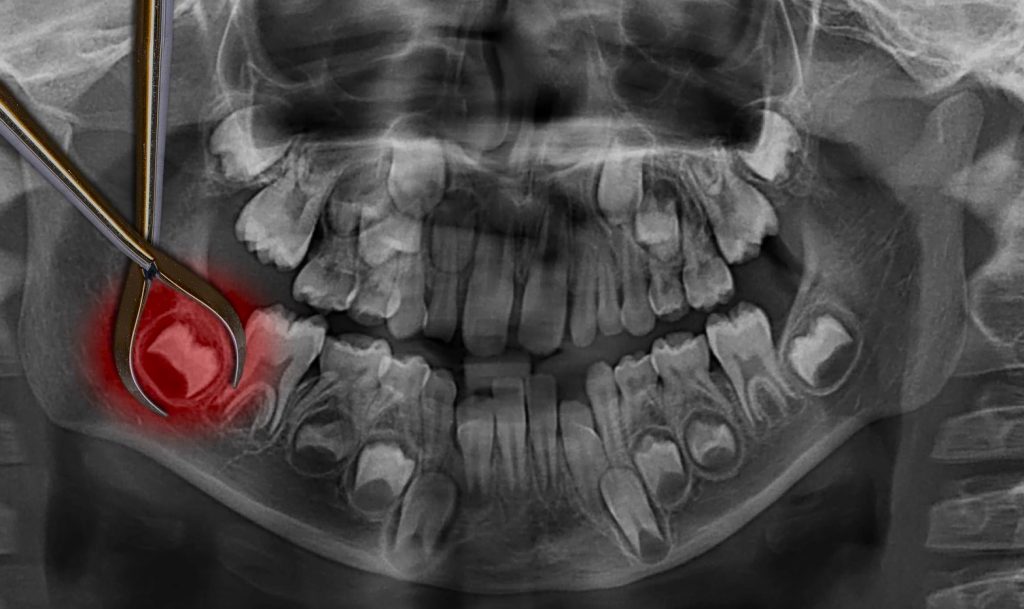

El dentista o cirujano maxilofacial comienza con una evaluación clínica y radiográfica (generalmente con radiografías panorámicas o 3D) para determinar la posición de las muelas de juicio, su tamaño y su grado de impacto. Esta evaluación es crucial para planificar la cirugía y anticipar posibles complicaciones.

Impactación: La causa más frecuente de extracción de muelas de juicio es la impactación. Esto ocurre cuando las muelas de juicio no tienen suficiente espacio para erupcionar correctamente. Pueden quedar atrapadas en la encía o en el hueso, lo que puede provocar dolor, infecciones y otros problemas dentales.

Infecciones o Quistes: En algunos casos, se forman quistes o infecciones alrededor de las muelas de juicio impactadas. Estos quistes pueden dañar el hueso y las raíces de los dientes cercanos.